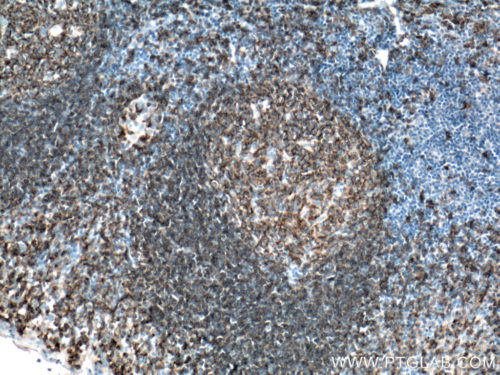

The two main types of lymphocytic leukemia are chronic lymphocytic (CLL) and acute lymphocytic (ALL). Patients have elevated levels of lymphoblasts (precursors of white cells) in their blood. These can be either T or B cell lineage. CD3 (Figure 1), CD4, and CD8, as classic markers of T cells, are a good prognostic marker of patient survival (PMID: 20846097). CD19 (Figure 2), an antigen widely present on B cells, persists in its expression on B cell-related cancer cells. It is often used in diagnosis (PMID: 8528044). Additional markers, namely CD20 (Figure 3), CD22, CD24, and CD79a, are used to study minimal residual disease – drug-resistant leukemic cells (PMID: 9492773). Plasma membrane staining of CD38 (Figure 4) and CD49d is often used in the clinic and their expression correlates with the disease severity and its response to chemotherapy (PMID: 10477712). ZAP70, an intracellular protein, is also a predictor of leukemia. It is involved in promoting prolonged signaling of the BCR pathway and the survival of cancer cells (PMID: 18577710).